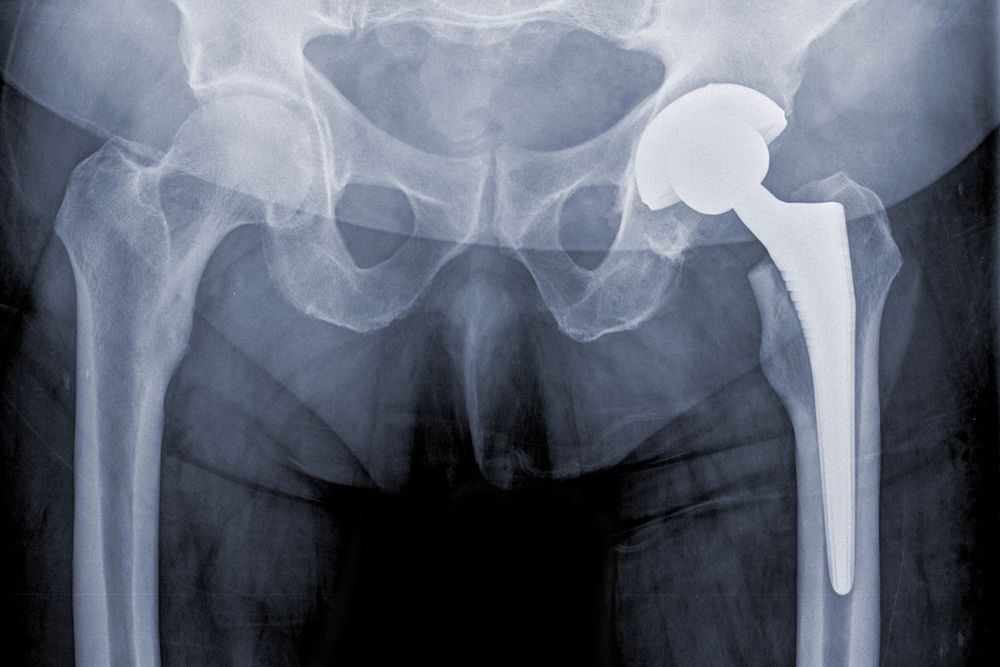

Medical devices can range from those that are implanted into our bodies, such as hip replacement systems, to those that we use externally, such as wheelchairs. Some of the more common medical devices to experience defects include:

- Hip replacement systems

Defective medical devices, particularly those that are implanted internally, can cause serious damage. Implants such as hip replacement systems and IVC filters can break and the pieces can migrate. This can cause damage to the internal organs. Other devices, like medical blankets, can harbor bacteria that can lead to serious infection. Still other devices, like a faulty wheelchair, can cause head injuries or broken bones. In the most severe of cases, injuries caused by a defective medical device can be fatal.